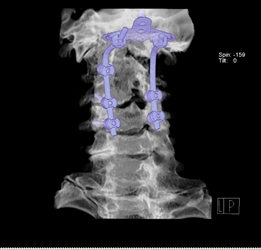

圖2示患者術后枕骨與頸椎體固定良好。